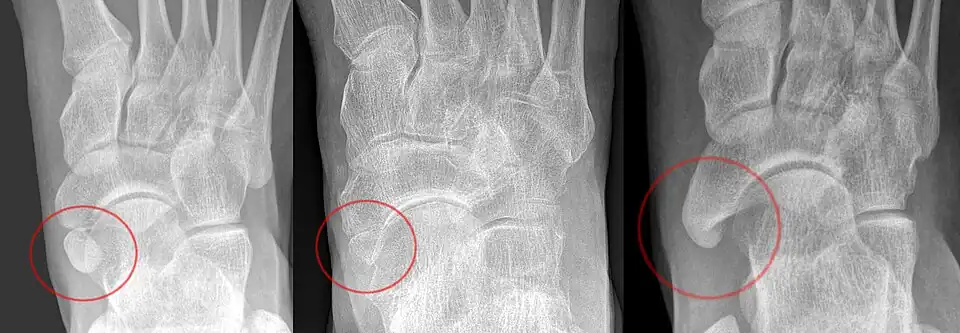

X-ray of the foot showing an accessory navicular bone

The Geist classification divides the accessory navicular bones into three types.[3]

• Type 1: An os tibiale externum is a 2–3 mm sesamoid bone in the distal posterior tibialis tendon. Usually asymptomatic.

• Type 2: Triangular or heart-shaped ossicle measuring up to 12 mm, which represents a secondary ossification center connected to the navicular tuberosity by a 1–2 mm layer of fibrocartilage or hyaline cartilage. Portions of the posterior tibialis tendon sometimes insert onto the accessory ossicle, which can cause dysfunction, and therefore, symptoms.

• Type 3: A cornuate navicular bone represents an enlarged navicular tuberosity, which may represent a fused Type 2 accessory bone. Occasionally symptomatic due to bunion formation.

Radiological images